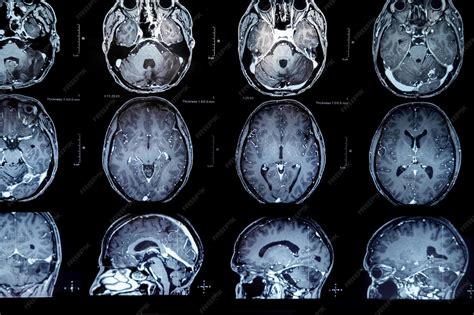

Resonancia Magnética Craneal

La RM craneal utiliza un campo magnético y ondas de radio para obtener imágenes detalladas del cerebro y los tejidos nerviosos circundantes. Es esencial para la detección de tumores, trombosis venosas, esclerosis múltiple (EM), infartos y otras alteraciones del sistema nervioso central (SNC), incluyendo la sustancia blanca, la fosa posterior y el tronco del encéfalo.

En algunos casos, se puede recomendar no comer ni beber nada de 4 a 6 horas antes de la prueba. La resonancia magnética funcional (RMF), una modalidad más reciente, mide los cambios metabólicos en el tejido cerebral en actividad, ayudando a localizar con precisión las áreas responsables de funciones como el habla, la memoria, la audición, la sensibilidad y el movimiento, lo cual puede variar entre individuos.